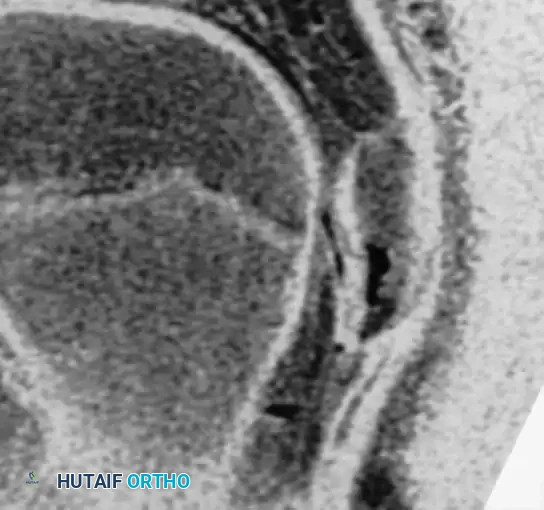

Osteochondritis dissecans (OCD) of the ankle primarily affects the talar dome. The natural history of this lesion in children with open physes is highly favorable compared to adult populations.

Natural History and Imaging

Bauer et al., in a long-term follow-up study (≥ 20 years) of 30 children with ankle osteochondritis, found that only one patient developed severe osteoarthritis. The vast majority experienced complete healing with only minor residual radiographic changes. This is in stark contrast to osteochondritis of the knee, where secondary osteoarthritis is a frequent complication.

Radiographic and MRI evaluation of osteochondral lesions of the talar dome, demonstrating subchondral separation and surrounding edema.